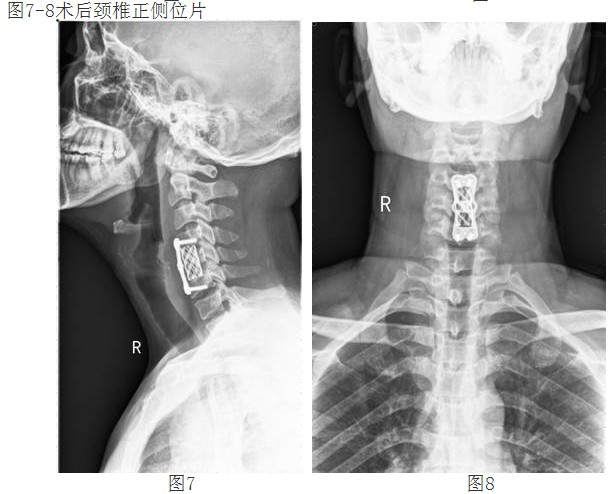

經(jīng)過譚主任和全科醫(yī)護(hù)人員充分的術(shù)前準(zhǔn)備和討論,對(duì)患者實(shí)施了頸椎前路頸4/5、頸5/6椎間盤摘除、頸5椎體次全切除、椎管減壓鈦網(wǎng)植骨融合、頸前路鈦板固定術(shù)。手術(shù)取得了成功。術(shù)后第二天,李阿婆的四肢麻木就明顯減輕,握手能力和手臂力量都明顯好轉(zhuǎn)。

譚主任介紹,重度頸椎病手術(shù)治療難度大風(fēng)險(xiǎn)高,一旦脊髓神經(jīng)和骨質(zhì)鈣化韌帶相粘連,手術(shù)用力稍有不當(dāng),就會(huì)損及脊髓而造成終身癱瘓。脊柱外科成立以來,頸椎前后路手術(shù)已陸續(xù)開展,三年前在廣東省中醫(yī)院和中山醫(yī)一、二院教授指導(dǎo)下完成,2011年我科已經(jīng)成功獨(dú)立完成了多例頸椎病手術(shù),現(xiàn)在我科在該技術(shù)已趨向成熟,頸椎前路手術(shù)是目前治療脊髓型頸椎病可靠而有效的方法之一,它具有直視下減壓徹底、出血少、創(chuàng)傷小等優(yōu)點(diǎn),有利于術(shù)后脊髓神經(jīng)的恢復(fù)。

經(jīng)頸前路減壓植骨融合內(nèi)固定術(shù)屬復(fù)雜高難度高風(fēng)險(xiǎn)手術(shù),該技術(shù)的成功開展,填補(bǔ)了我院在該領(lǐng)域的空白,表明我院脊柱外科技術(shù)邁上了更高的臺(tái)階。(后附典型病例照片)